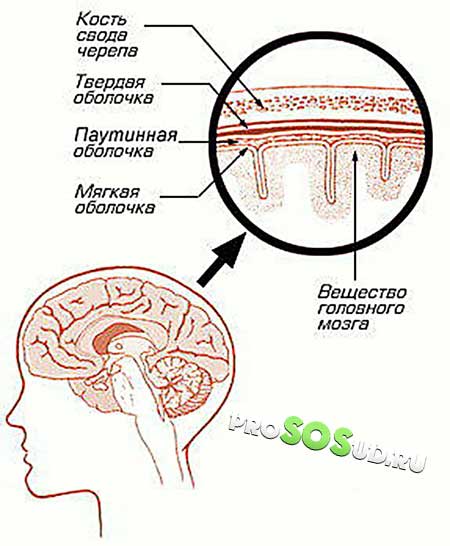

Арахноидит, затрагивающий головной или спинной мозг, представляет собой серозное воспаление уникальной структуры, находящейся между твердой верхней оболочкой и глубокой мягкой. Эта структура, напоминающая тонкую паутину, и получила название паутинная оболочка. Она образована соединительной тканью и образует настолько тесную связь с мягкой оболочкой мозга, что их часто рассматривают как единое целое.

Паутинная оболочка отделена от мягкой оболочки субарахноидальным пространством, в котором находится спинномозговая жидкость. В этом пространстве располагаются кровеносные сосуды, обеспечивающие питание данной структуры.

Из-за особенностей своего строения воспаление паутинной оболочки не бывает локализованным и охватывает всю систему. Инфекция может проникать сюда через твердую или мягкую оболочку.